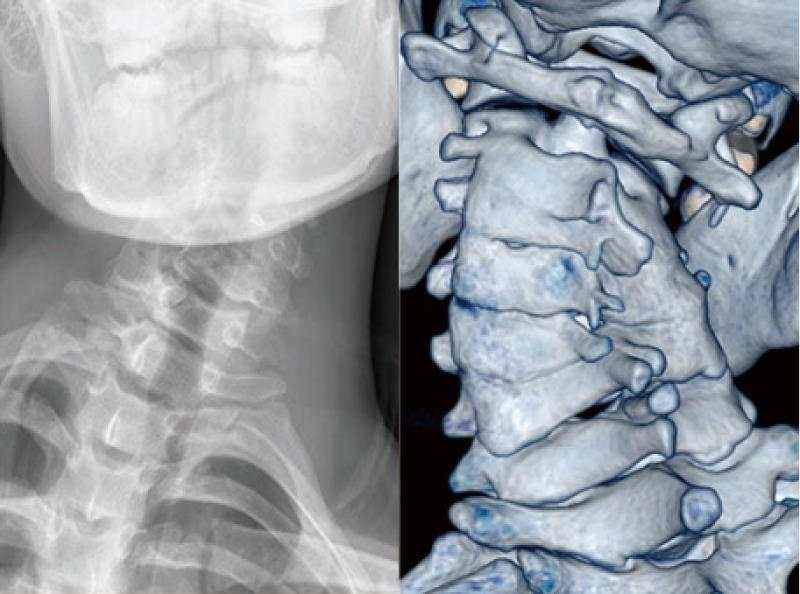

病例4: 颈椎骨性斜颈矫形术

骨性斜颈,术前X线和CT示颈椎半椎体合并椎体分隔不全畸形

颈椎前路后路联合截骨矫形术,随访X线和CT示矫形效果满意。